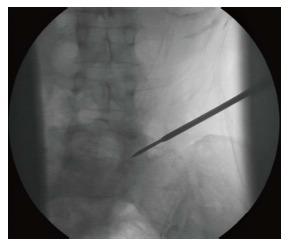

Transforaminal Percutaneous Endoscopic Discectomy (TPED) is a minimally invasive technique mainly used for the treatment of lumbar disc herniation from a lateral approach. Performed under local anesthesia, TPED has been proven to be a safe and effective technique which has been also associated with shorter rehabilitation period, reduced blood loss, trauma, and scar tissue compared to conventional procedures. However, the procedure should be performed by a spine surgeon experienced in the specific technique and capable of recognizing or avoiding various challenging conditions. In this review, pitfalls that a novice surgeon has to be mindful of, are reported and analyzed.

经椎间孔入路经皮内镜下椎间盘切除术(TPED)是一种主要用于从侧方入路治疗腰椎间盘突出症的微创技术。TPED在局部麻醉下进行,已被证明是一种安全有效的技术,与传统手术相比,它还具有康复期短、失血少、创伤小和瘢痕组织少的特点。然而,该手术应由精通该特定技术且能够识别或避免各种具有挑战性情况的脊柱外科医生进行。在本综述中,报告并分析了新手外科医生必须注意的陷阱。